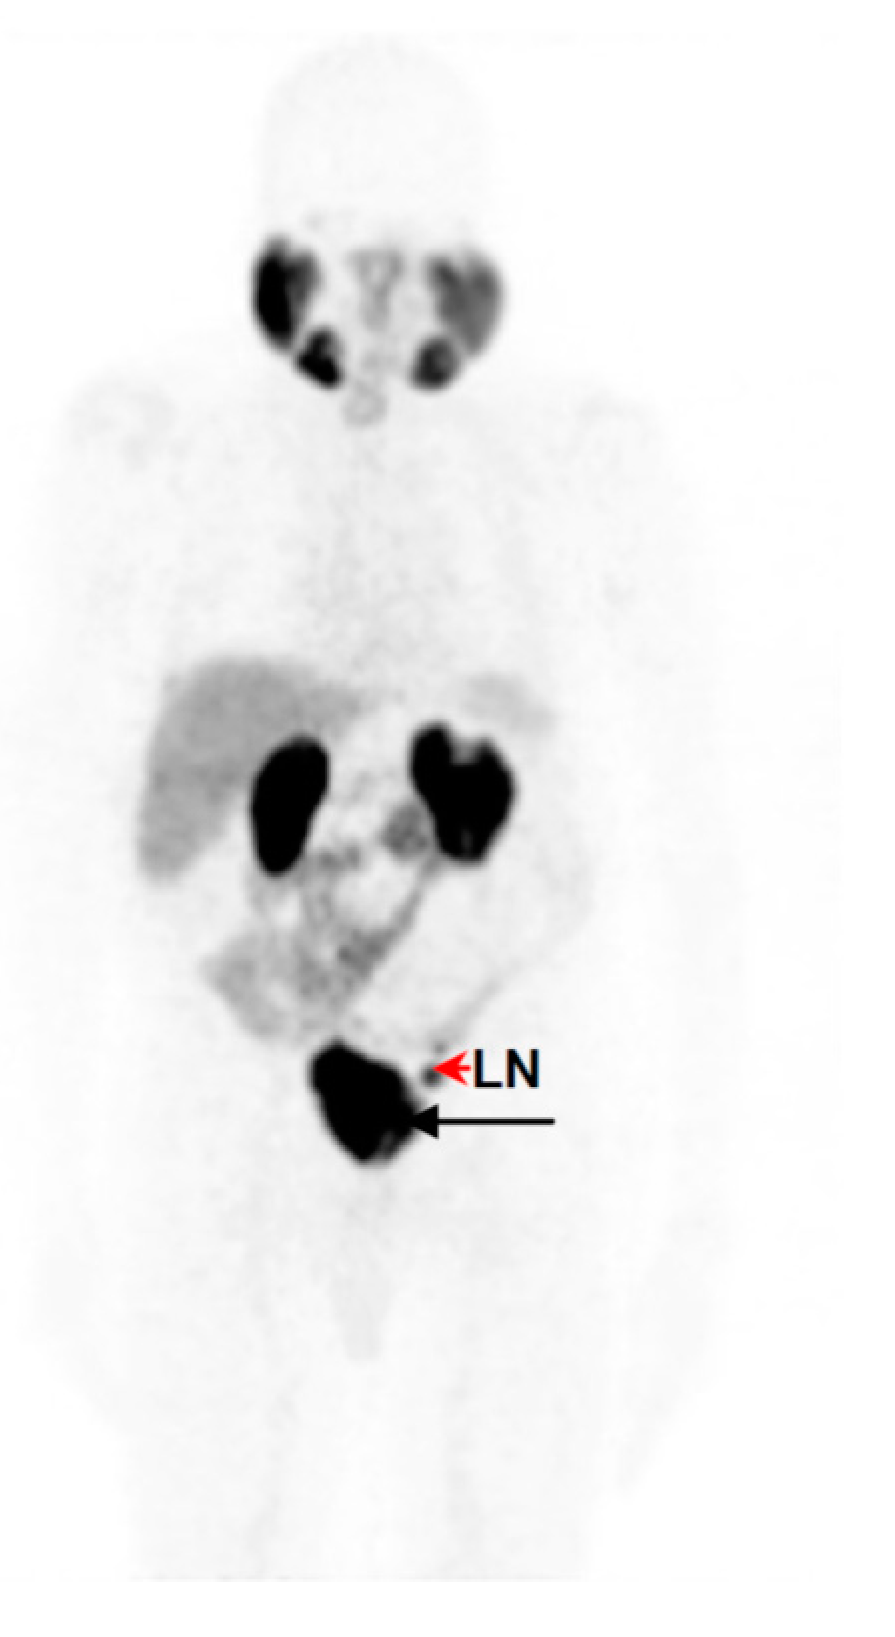

2.5. Clinical PET/CT—68Ga-DKFZ-PSMA-11 Kit Performance in Prostate Cancer Patients

Image Acquisition, Reconstruction and Analysis